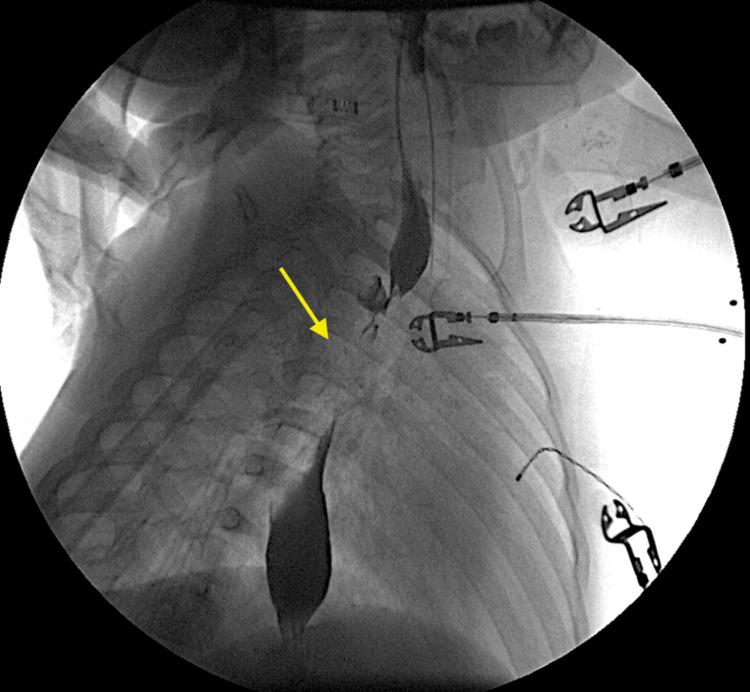

Congenital esophageal stenosis (CES) is an uncommon condition that poses diagnostic and therapeutic challenges due to its rarity and clinical presentation similar to other esophageal disorders. Symptoms typically start with dysphagia around the introduction of solid foods. A broad range of potential differential diagnoses contributes to a delay in obtaining a definitive diagnosis and administering the proper treatment. We report a two-year-old boy who presented with difficulty swallowing solid foods since 11 months of age, manifesting as choking and gagging. Initial evaluation revealed a double esophageal web, with proximal stenosis detected in an esophagram. Despite two endoscopic dilations and cauterization of the proximal web, a second web in the middle third of the esophagus was found. Subsequent dilatation successfully improved symptoms, and the child began tolerating table foods. This case report aims to contribute to the limited existing literature on CES and to add to the clinical practice in the diagnosis and treatment of this uncommon congenital anomaly.

先天性食管狭窄(CES)是一种罕见的疾病,由于其罕见性以及临床表现与其他食管疾病相似,给诊断和治疗带来了挑战。症状通常在开始摄入固体食物时以吞咽困难为首发表现。众多潜在的鉴别诊断导致确诊和给予恰当治疗出现延迟。我们报告一名两岁男孩,自11个月大起就出现吞咽固体食物困难,表现为呛噎和作呕。初步评估发现一个双食管蹼,食管造影显示近端狭窄。尽管进行了两次内镜扩张并烧灼近端蹼,但在食管中三分之一处又发现了第二个蹼。随后的扩张成功改善了症状,患儿开始能够耐受固体食物。本病例报告旨在为关于CES的有限现有文献做出贡献,并为这种罕见先天性异常的诊断和治疗临床实践增添内容。